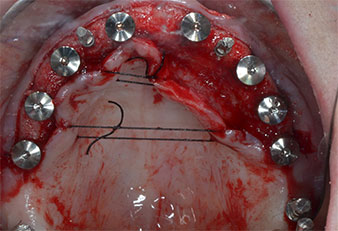

Debido al hueso relativamente duro (D2) existente en el sector anterior, los sitios de los implantes largos de 10 mm de las posiciones 11 y 21 se finalizaron con una fresa rotatoria de 4 mm de diámetro, en combinación con un contra-ángulo quirúrgico WS-75 L de W&H, el motor de implantes Implantmed de W&H y el módulo opcional Osstell ISQ de W&H. En cambio, debido a la existencia de hueso blando, los sitios posteriores se prepararon hasta un diámetro final de 3 mm utilizando el inserto Piezomed I3P. Por último, los implantes se colocaron a nivel crestal para su osteointegración durante tres meses (figuras 6-10). La prótesis existente se mantuvo sobre cuatro implantes provisionales (figura 8).

Otro aspecto importante de la preparación piezoeléctrica es la excelente sensibilidad del cirujano en volúmenes óseos pequeños, como sucedió en el caso de la paciente que hemos descrito aquí. También nos permite corregir la angulación del lecho óseo con todos y cada uno de los instrumentos antes de la colocación del implante.

La paredes óseas corticales delicadas, que se encuentran con frecuencia en sitios anteriores, son más fáciles de detectar con sistemas piezoeléctricos, lo que permite una preparación menos invasiva y menor pérdida de hueso posterior a la intervención. Además, el sistema de refrigeración del Piezomed permite una irrigación eficaz del sitio quirúrgico, lo que evita la generación de calor, en combinación con una eficacia máxima.